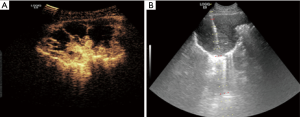

In the study, linear and non-linear two puncture paths were employed, we first tried to puncture along traditional linear path in all lesions, if an attempt to puncture the lesions directly failed due to be blocked by the ribs and then changed to puncture along non-linear path instead (Figure 2). (I) The traditional linear path: needle insertion point on skin was at the center of intercostal space with the nearest distance to the lesion and the lesion displayed clearly. A needle tract was designed to pass through the needle insertion point and the target area of the lesion, being coincidence with built-in puncture guide line. Then the puncture needle was put into the needle groove of the guide device and the whole biopsy process was guided by real-time ultrasound; (II) non-linear path: if an attempt to puncture the lesion directly along linear path failed due to be blocked by the rib along linear path and then changed to puncture along non-linear path instead. The needle insertion point on skin remained unchanged, the puncture needle subverticaly descended through the intercostal space down to the inner intercostal muscle layers, then tilting the probe with puncture needle properly to make the direction of the needle in line with the preset puncture guide line across the target lesion, then puncture needles were penetrated into the lesion along the guide line under real-time guidance of ultrasound and specimens were obtained.

The needle insertion angle is mainly dependent on the position of the lesion. According to needle insertion angle along linear path, lesions were divided into 70°~80° angle group and 80°–90° angle group in our study, the success rate of biopsy procedure along linear puncture was significantly higher at angle of 80°–90°group (93.0% vs. 20.4%, P<0.01), and the adoption rate of non-linear path biopsy for solving the puncture needle blocked by the ribs was significantly higher at angle of 70°–80°group (93.0% vs. 20.4%, P<0.01). In the study, the problem of puncture needles blocked by the ribs along linear path biopsy was completely solved using non-linear path biopsy, which was attributed to the fact that the lesions at 80°–90° subvertical angle needle insertion usually located in the intercostal space and biopsy along linear path had a high successful rate, while lesions at an angle of 70°–80° needle insertion usually located behind the ribs and biopsy along non-linear path was appropriate. Therefore, in percutaneous ultrasound-guided biopsy for peripheral lung lesions, the angle of needle insertion may serve as a reminder of the appropriate puncture path.

In percutaneous ultrasound-guided biopsy for peripheral lung lesions, the problem of puncture needles blocked by the ribs is a frequent occurrence, especially for lesions located behind the ribs. Ultrasound image has poor resolution for needle tips and lesions and chest wall compared with CT image influenced by the aerated lung, so, regardless of anatomical features of peripheral lung lesions and the chest wall, blindly trying can easily lead to biopsy failure and increase the incidence of complications and is not advisable In the study, the needle was firstly punctured along traditional linear path in all lesions, if the needle tip happened to be blocked by the rib and then changed to puncture along non-linear path instead. In percutaneous ultrasound-guided biopsy for peripheral lung lesions, puncture biopsy along linear path by real-time guidance of ultrasound is most commonly performed, simple and convenient, preferable for lesions located in the intercostal space, but prone to failure for lesions located behind the ribs, we solved this problem well using “non-linear path” puncture technique. The over all adoption rate of non-linear path biopsy is 45.7% (42/92) in the paper. Obviously, “linear” and “non-linear” puncture path are suited for lesions located in the intercostal space and behind the ribs respectively, which are equally important skills in ultrasound-guided needle biopsy for peripheral lung lesions.